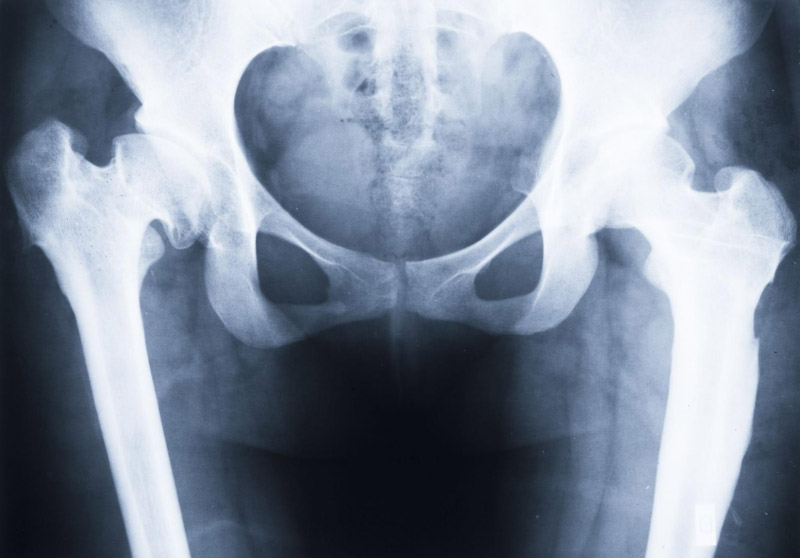

Cấp độ 4 – Nghiêm trọng: Khe khớp biến mất hoàn toàn, xuất hiện gai xương lớn, biến dạng nghiêm trọng tại đầu xương đùi và ổ cối.

Viêm khớp nghiêm trọng ở cả hai bên, hoại tử vô mạch khớp hông.Viêm khớp háng nặng ở cả hai bên.